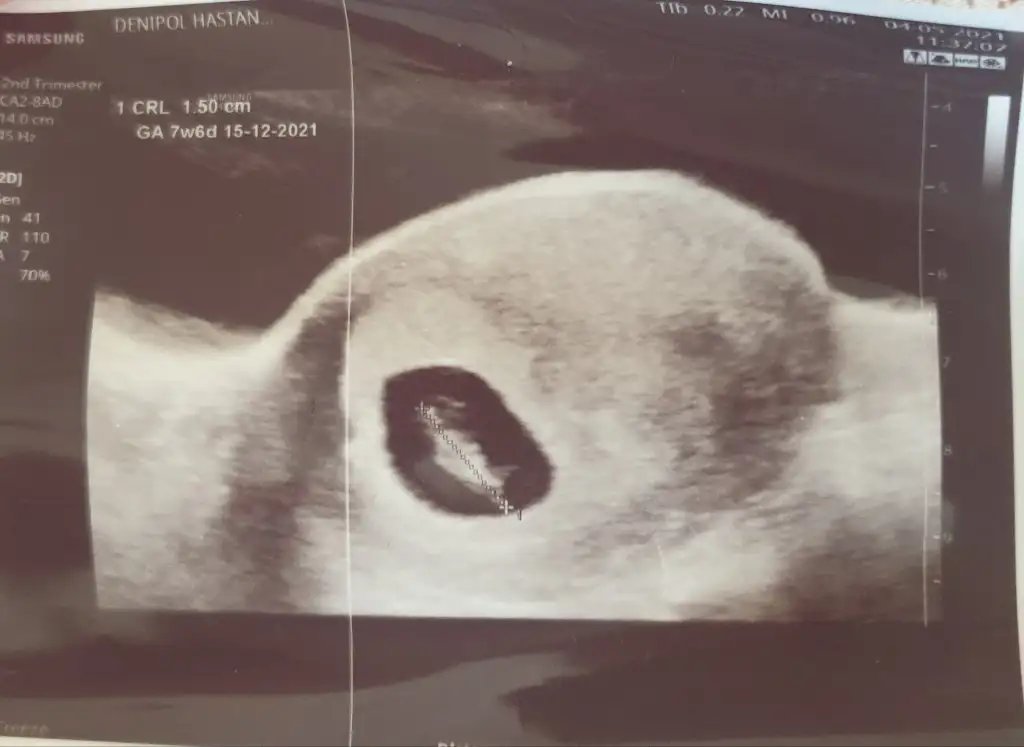

Ramzi teorisi okudum yüzde 97 dogruymuş.Ama neye göre bakcam ultrasona bilemedim. Size sormak istedim Bebeğim sağa daha yakın sanki bası da solda ayakları sağa bakıyor yani. Anlamadım ben. Sağlıklı olsun tabi kız erkek fark etmez ama merak ettim. İlk foto 5+5 iken 2.foto 9+3ken

Tabiki 7 8 haftalik ultrason kagidi varsa at alttan mi ustten mi soyle tahmin yapayim canimBanada bakarmısınız acaba rica etsem